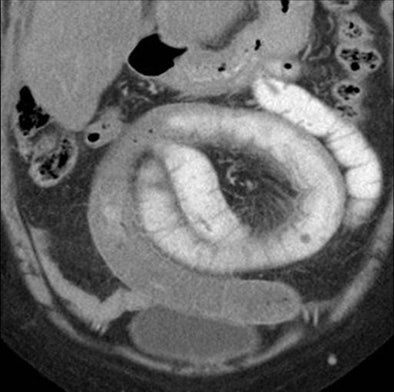

| Above, small-bowel obstruction diagnosed with both oral and IV contrast. Below, another patient with small-bowel obstruction diagnosed with IV contrast alone. All images courtesy of Dr. Stephan Anderson. |

![]() |

| Above, small-bowel obstruction diagnosed with both oral and IV contrast. Below, another patient with small-bowel obstruction diagnosed with IV contrast alone. |